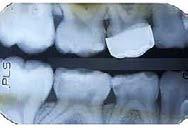

Estudios radiográficos iniciales

En la radiografía lateral de cráneo se ve el diagnósitico: clase II esqueléti ca, con crecimiento hiperdivergente, mordida profunda anterior (Figura 4).

Estudios radiográficos de inicio en la radiografía lateral de cráneo (Figu ra 5) tenemos la clase II esquelética con un ANB de 7°, hiperdivergencia, aumento de la altura facial anterior, disminución de la altura facial poste rior y proclinación del incisivo supe rior con 1 a plano palatino de 121° e incisivo inferior de 1 a plano mandi bular de 99°.

En la radiografía panorámica (Figu ra 6) se observan 32 dientes, con los terceros molares en formación, adicionalmente la molar 46 con una